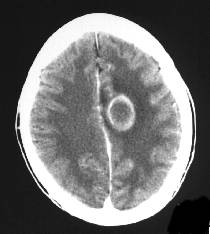

Computed tomographic scan CT scan is not as sensitive as MRI for the diagnosis of brain abscess but can frequently be obtained more easily on an emergent basis. When looking for a brain abscess, this study must be performed with a contrast agent. The lesion has different appearances depending upon its age: